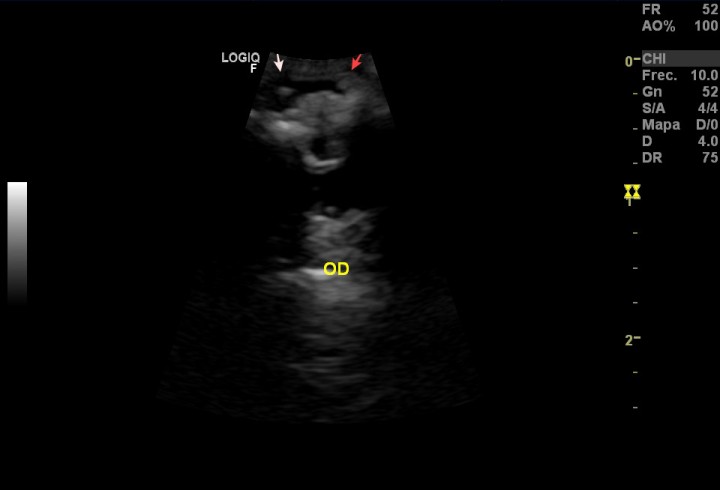

Se realizó una ecografía ocular (OD) (Scil Logic F3 con sonda micro-cóncava de 10 MHz) en la que se observó que el cristalino presentaba hiperecogenicidad e irregularidades, compatibles con una catarata hipermadura. De las dos estructuras localizadas en la cámara anterior, una de ellas se encontraba en la zona del ángulo iridocorneal, que dificultaba probablemente el drenaje del humor acuoso (Fig. 2). No existían alteraciones en la cámara posterior.

<p>Imagen de ecografía ocular (OD). Se aprecian dos masas en la cámara anterior (flechas), una de ellas en la zona del ángulo iridocorneal (flecha roja).</p>

Figura 2

Imagen de ecografía ocular (OD). Se aprecian dos masas en la cámara anterior (flechas), una de ellas en la zona del ángulo iridocorneal (flecha roja).